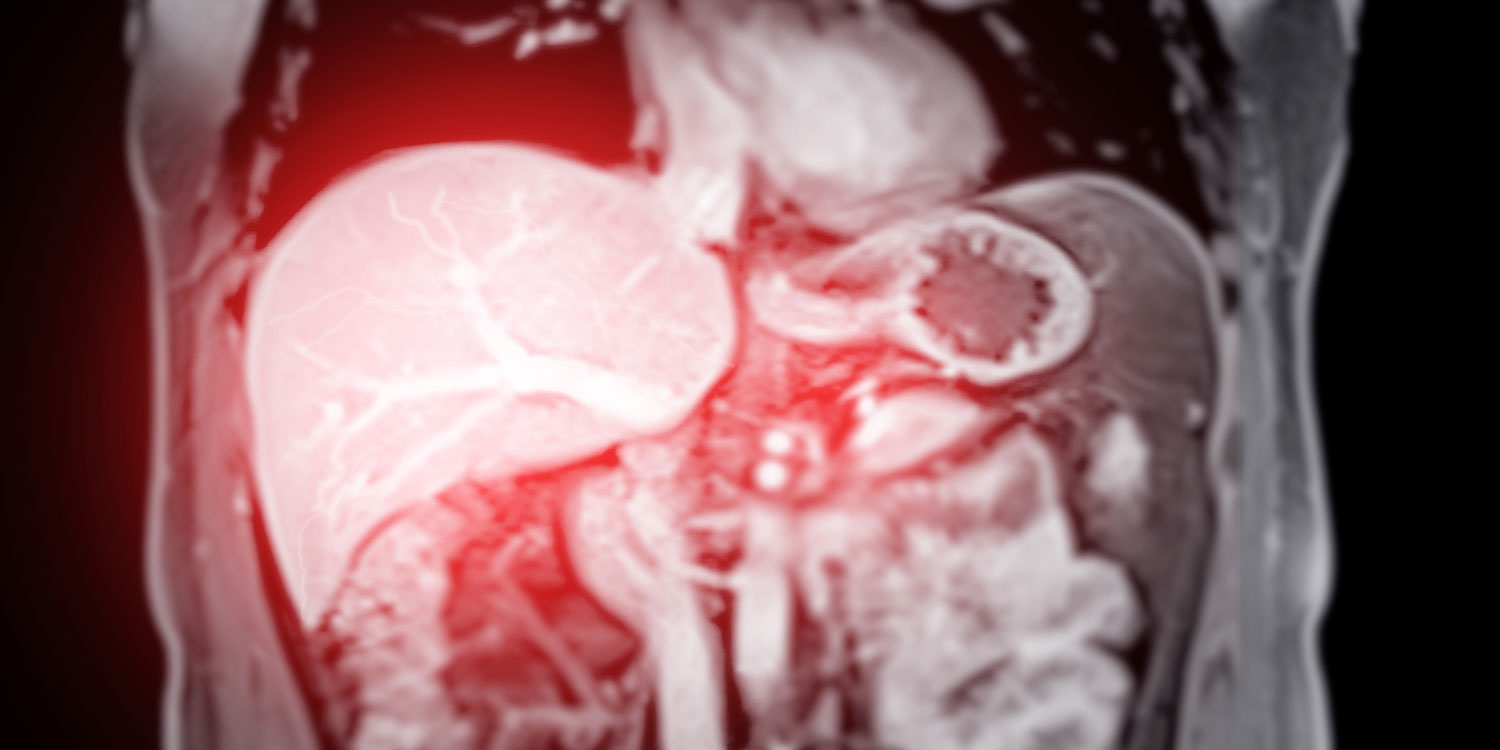

A liver MRI is a noninvasive imaging test that uses magnetic fields and radio waves to produce highly detailed pictures of your liver, bile ducts, blood vessels, and surrounding structures. Because the liver is composed largely of soft tissue and has a rich blood supply, MRI is ideally suited to reveal problems that may not be clearly visible on X-rays, ultrasounds, or even CT scans.

MRI abdomen coronal views are particularly useful for assessing liver, kidneys, and other abdominal organs with precision